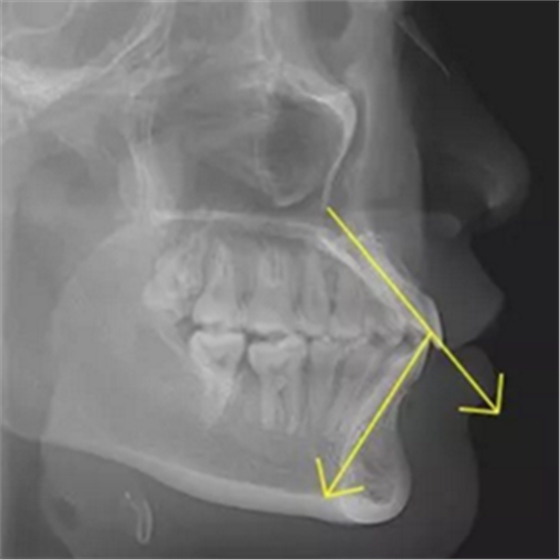

但前牙閉鎖合是上前牙下垂伸長,內(nèi)扣完全鎖住了下切牙,正面觀時我們常看不到下切牙,下切牙則常擁擠伸長咬到了上腭內(nèi)的牙齦上,上下前牙發(fā)生的交角幾近180°。

前牙閉鎖合交角